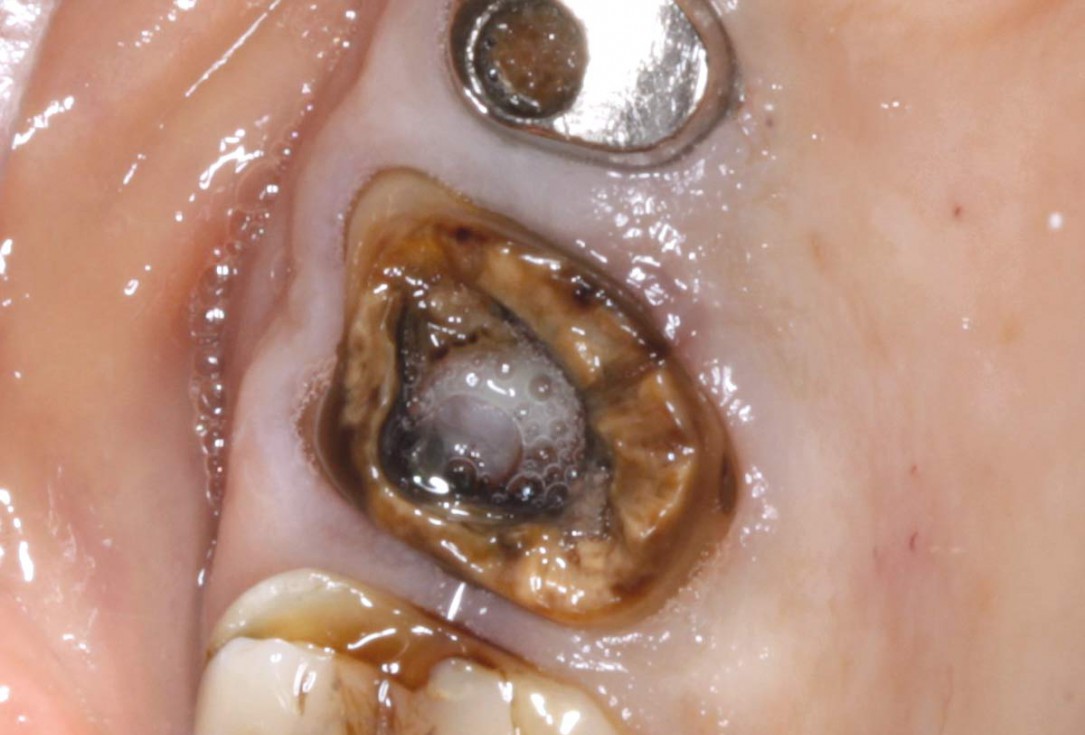

01/07 - Situation before tooth extraction.Socket preservation with permamem® - Dr. M. Turco